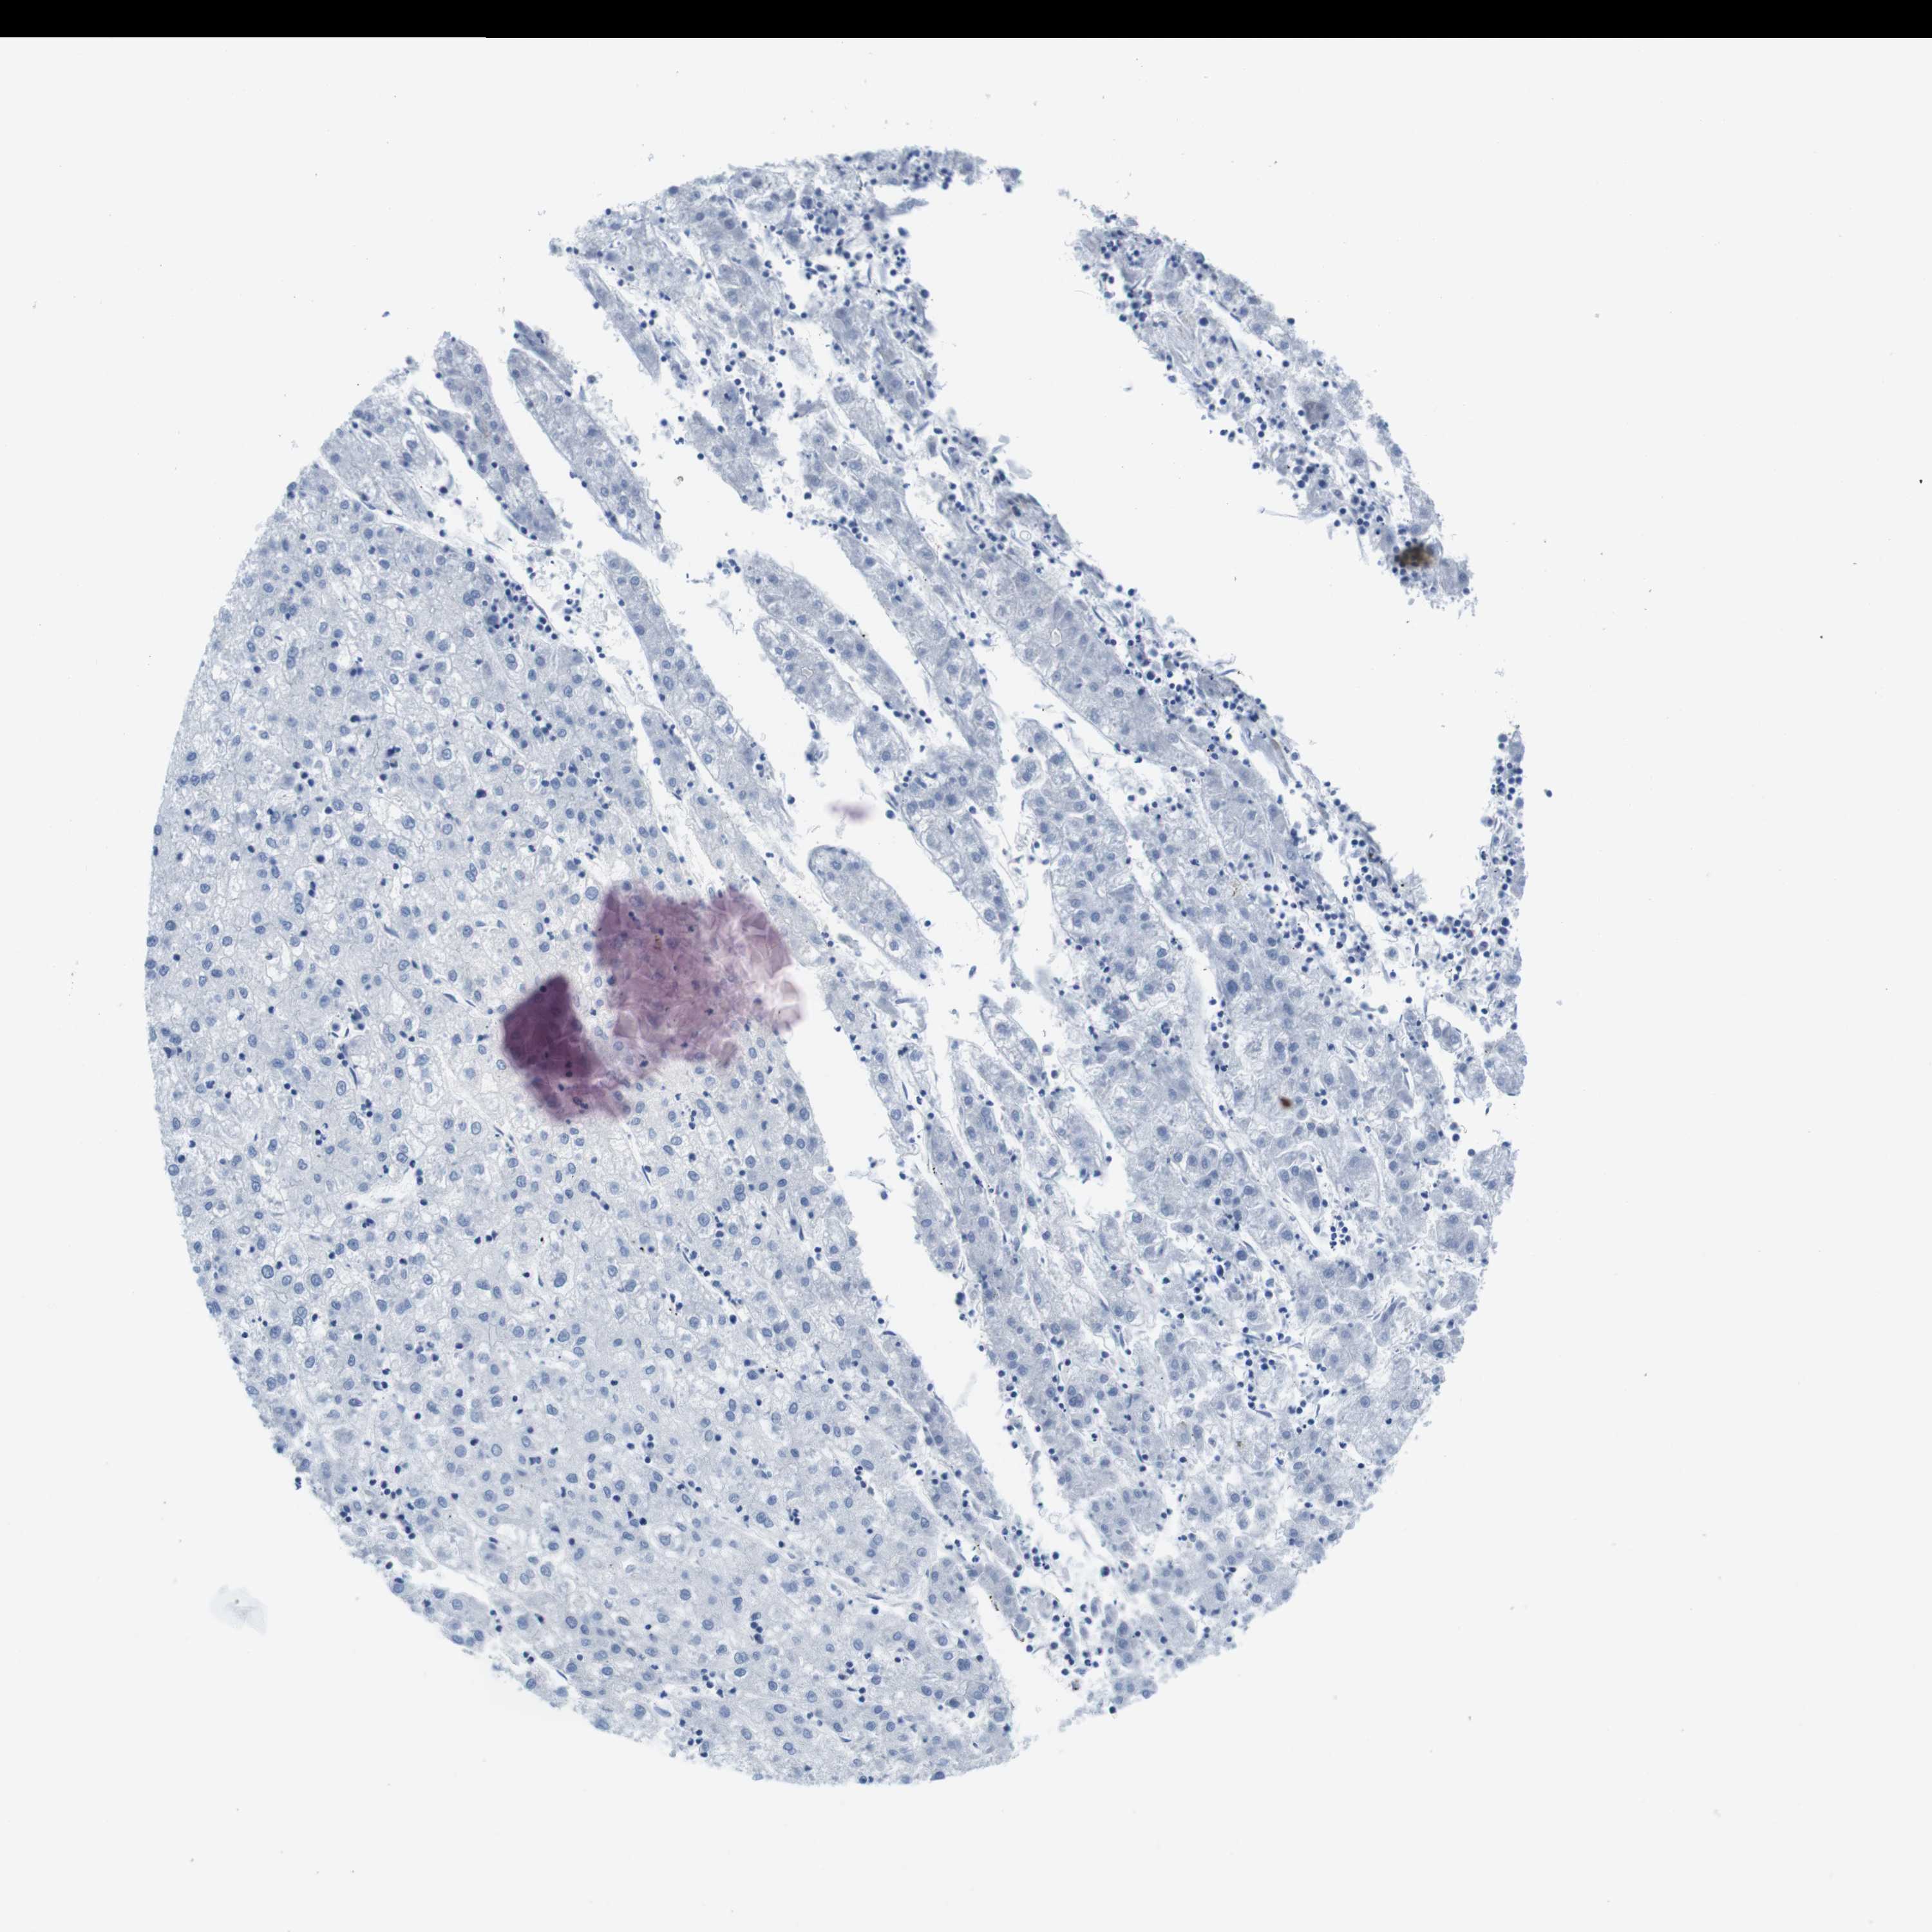

LIVER CANCER - Protein expressioni

A mouse-over function shows sample information and annotation data. Click on an image to view it in a full screen mode. Samples can be filtered based on level of antibody staining by selecting one or several of the following categories: high, medium, low and not detected. The assay and annotation is described here.

Note that samples used for immunohistochemistry by the Human Protein Atlas do not correspond to samples in the TCGA dataset.

Antibody stainingi

Antibody staining in the annotated cell types in the current human tissue is reported as not detected, low, medium, or high, based on conventional immunohistochemistry profiling in selected tissues. This score is based on the combination of the staining intensity and fraction of stained cells.

Each image is clickable and will lead to virtual microscopy that enables deeper exploration of all samples and also displays staining intensity scores, fraction scores and subcellular localization as well as patient and tissue information for each sample.

Antibody HPA039061

Antibody HPA039062

Antibody CAB015442

Antibody CAB022600

Cholangiocarcinoma

Carcinoma, Hepatocellular, NOS